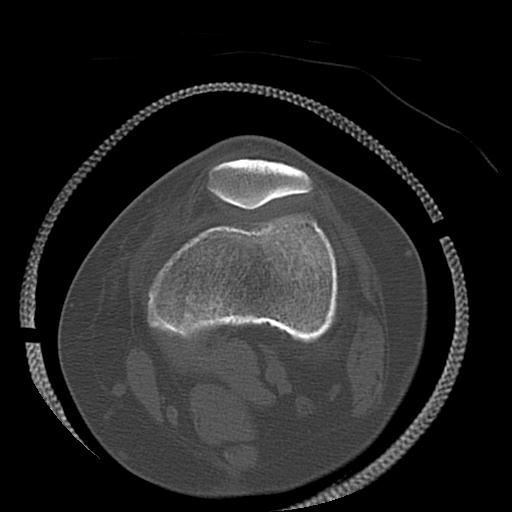

102755 1/4 2R 1/15 2R 右足関節 68歳女性 右三果脱臼骨折